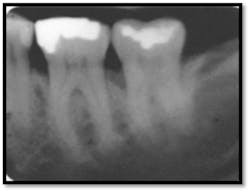

#26: 12mm MF and ML (above left); BOP, Class ll mobility (above right)

#19 presents with Class I furcation involvement

#18 presents with a mesial vertical defect and Class II furcation involvement